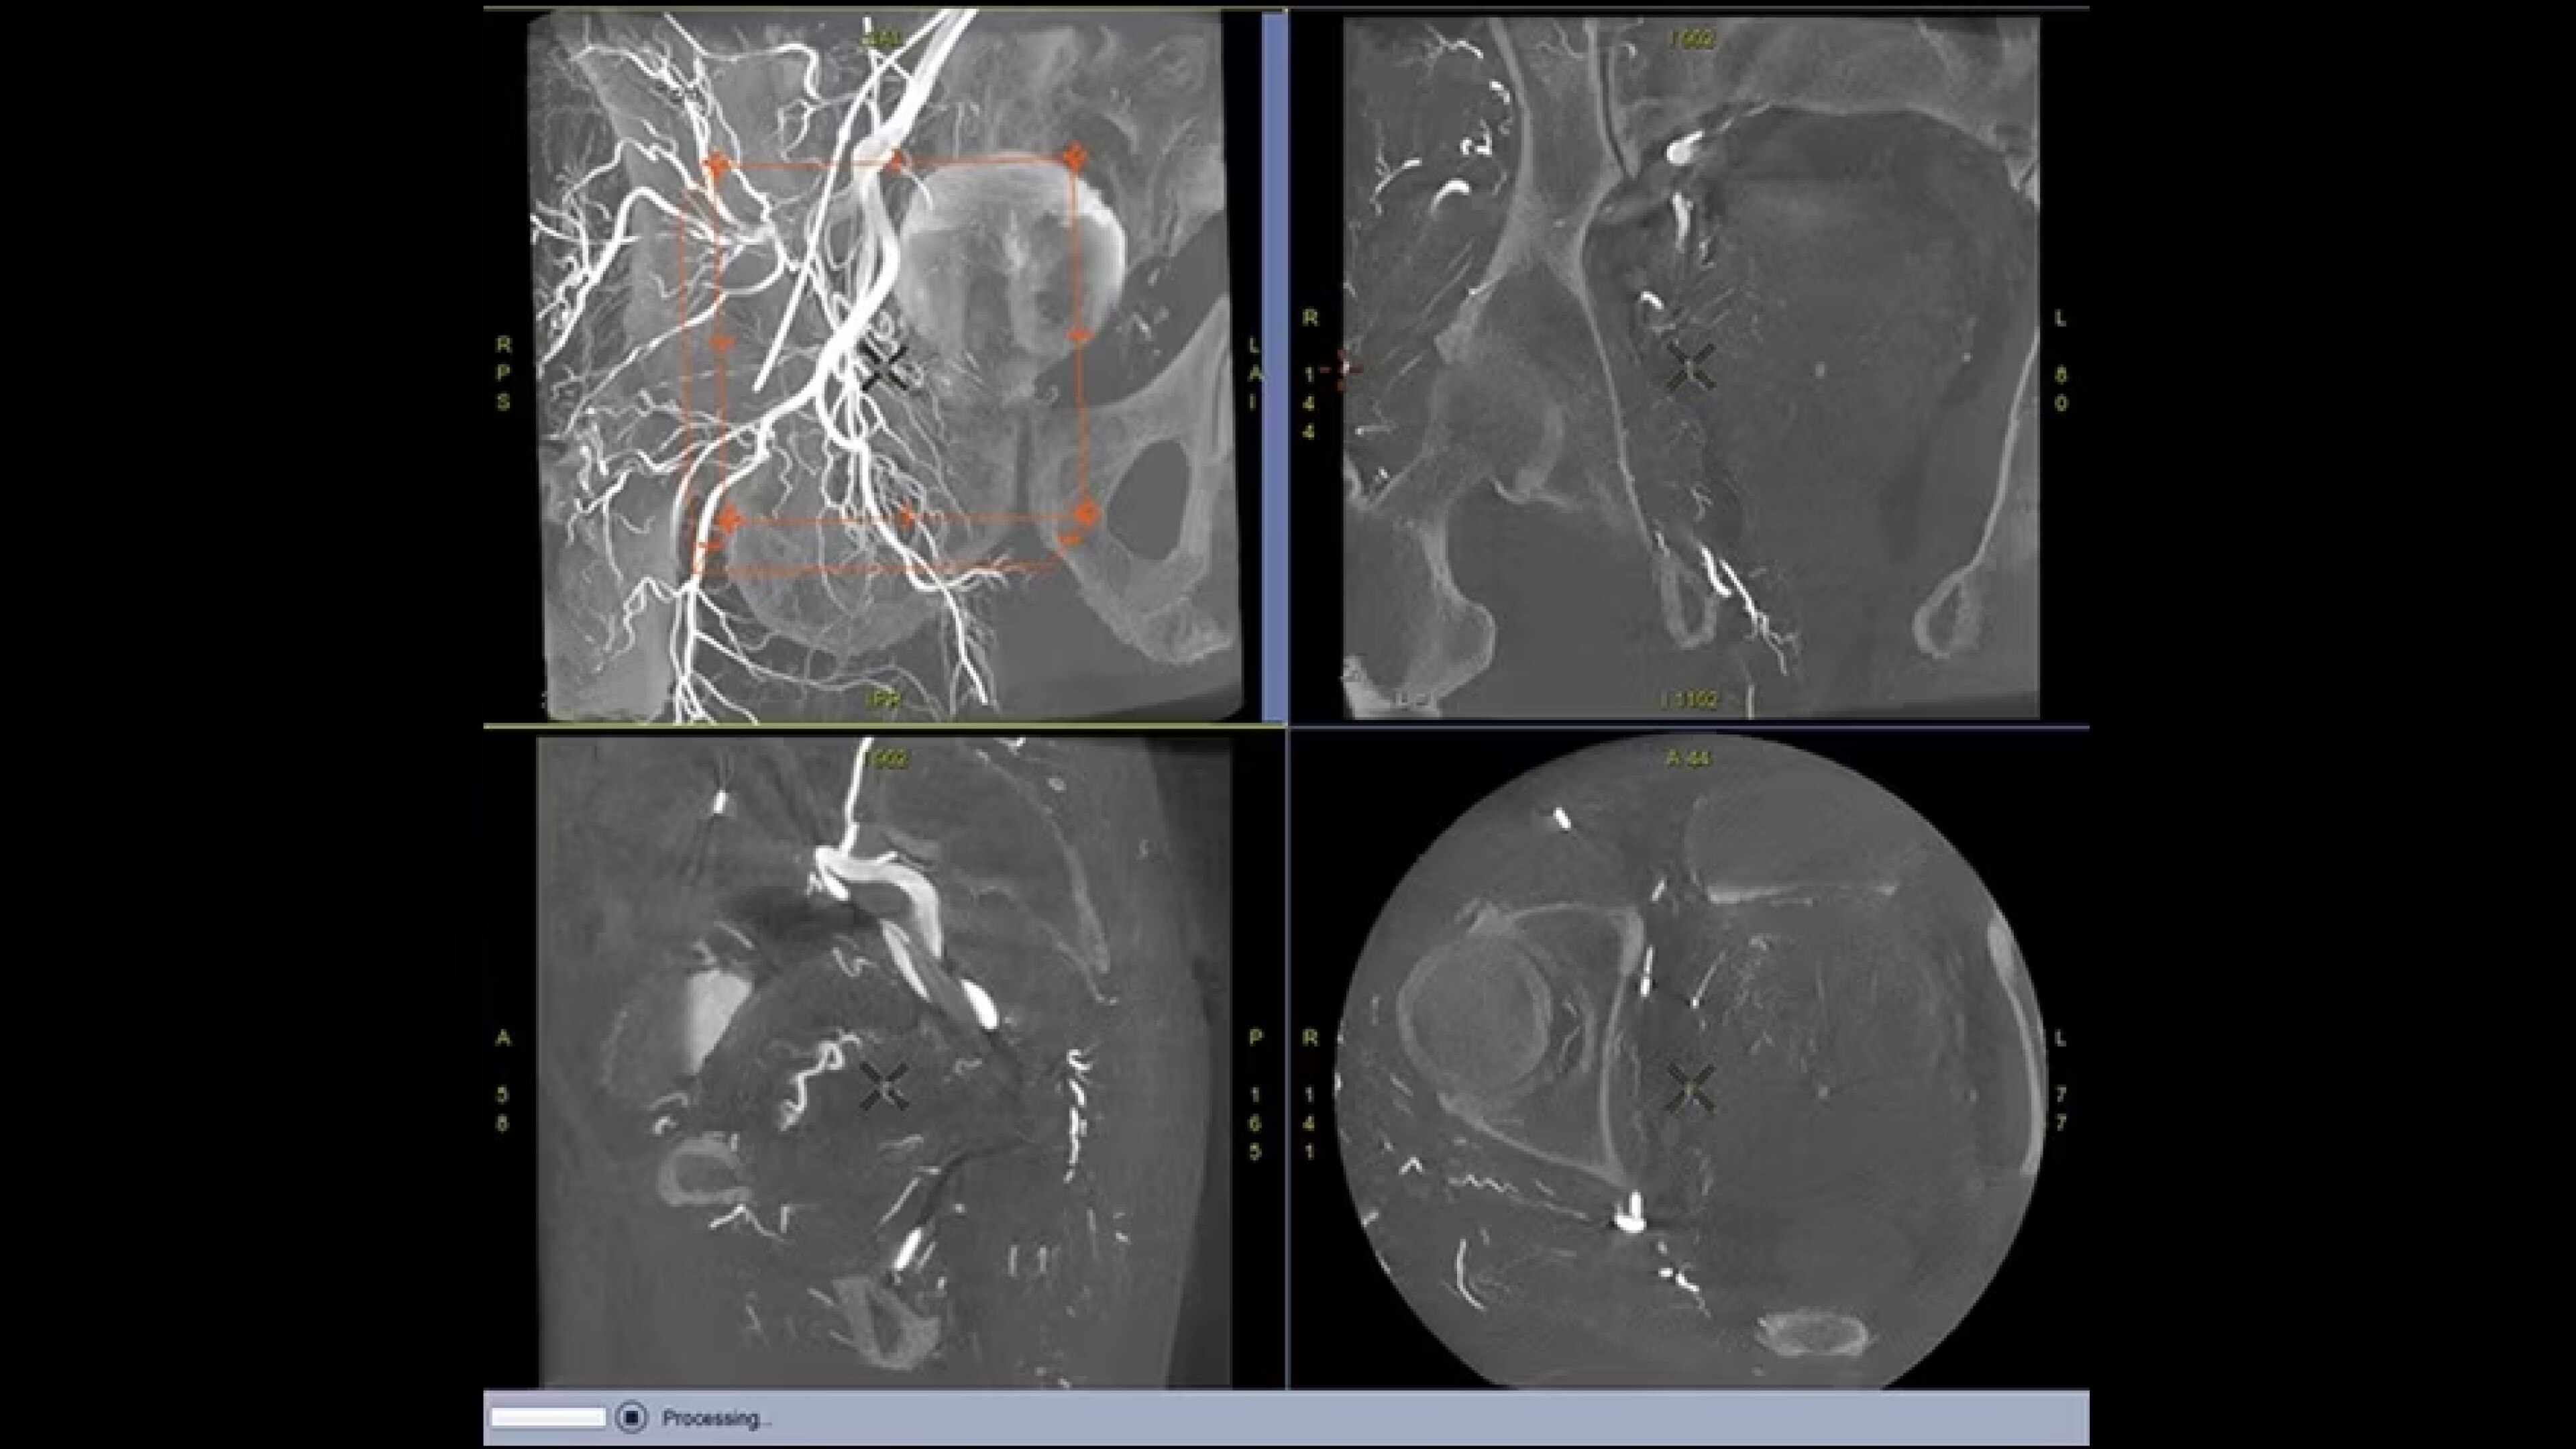

Correzione intelligente e automatizzata del movimento dell’intero cuore per immagini TC cardiache potenziate

Correzione del movimento

Riduzione degli artefatti da movimento fino a 6 volte1

Risoluzione temporale

Risoluzione temporale efficace di 19,5 millisecondi con velocità di rotazione del gantry di 0,23 s/giro2

Automatizzazione

Correzione automatica del movimento dell’intero cuore